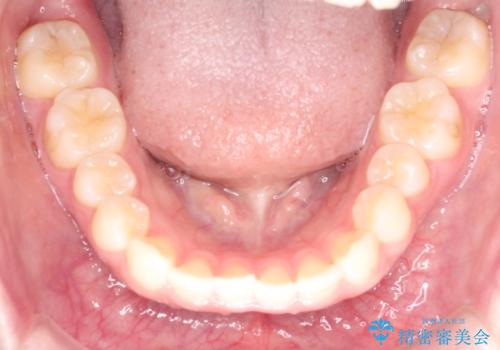

【インビザライン】前歯の凸凹をなおしたい

- 前歯のガタガタを主訴に来院されました。

インビザラインで綺麗な歯並びになり、患者さんには大変満足していただきました。